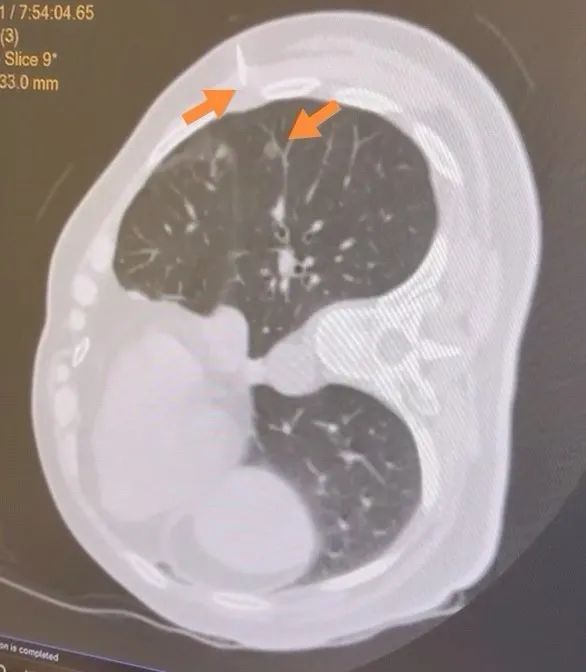

近日,北京积水潭医院胸外科收治一位女性患者, 6月前查体发现肺部结节,位于右肺下叶背段,为3mm磨玻璃结节(GGO),结节无明显实性成分,当时未做治疗,密切随访6月后复查胸部CT,结节进展为5mm结节,GGO伴部分实性成分。

箭头所指即为肿瘤位置

患者6个月随访期间肺部结节有进展性改变,而且结节位置不深(距离肺门较远),经胸腔镜肺楔形手术能够完整切除,切除后对患者肺功能影响较小,建议手术治疗。但是,5mm结节胸腔内定位非常困难,能否通过胸腔镜找到结节是一项非常具有挑战的事情。更雪上加霜的是:患者既往有结核性胸膜炎病史,术中胸膜广泛粘连的可能性非常大,给原本就微小的肿瘤定位又增加了难度。